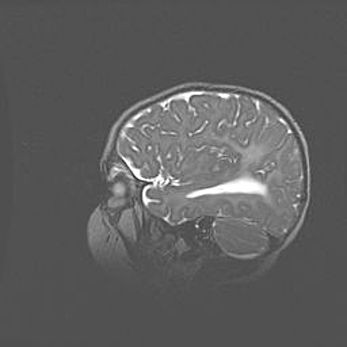

Сообщающаяся гидроцефалия. Кистозная энцефаломаляция головного мозга.

Возраст: 3 месяца 4 дня

Вес: 3100 г

Пол: женский

Окружность головы: 34 см

Срок гестации: 31 неделя

Кистозная энцефаломаляция головного мозга - одна из форм поражения головного мозга в детском возрасте. Характеризуется возникновением множественных и распространённых кист в коре, белом веществе и подкорковых образованиях головного мозга у плодов, новорождённых и детей раннего возраста. Развитие кистозной энцефаломаляции связано с внутриутробной асфиксией и гипотонией, родовой травмой, тромбозом синусов, пороками развития сосудов, инфекциями, сепсисом и другими причинами. Наиболее значимые инфекционные агенты: вирусы простого герпеса, цитомегалии, краснухи, токсоплазмы, энтеробактерии, золотистый стафилококк и другие.